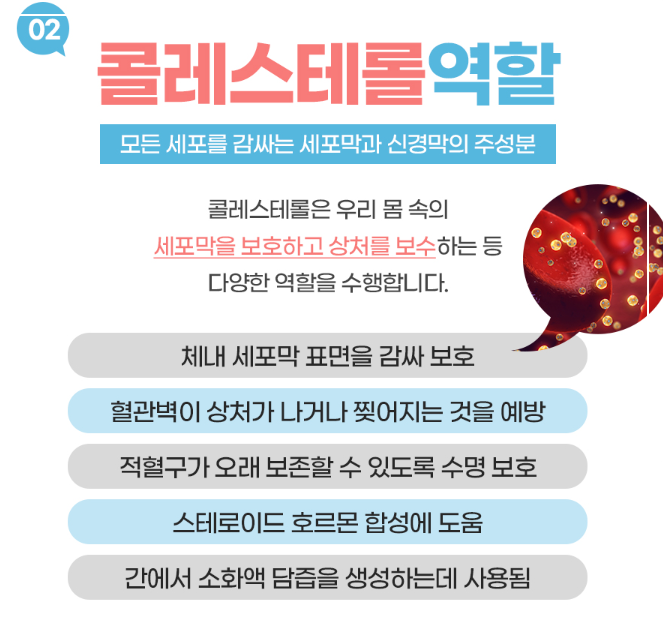

콤부차 효능 7: 콜레스테롤 수치 개선

콤부차는 심혈관 건강을 개선하는 데도 도움을 줄 수 있어요. 연구에 따르면 콤부차가 나쁜 콜레스테롤인 LDL-콜레스테롤과 지방의 흡수를 현저하게 지연시키고, 좋은 콜레스테롤인 HDL-콜레스테롤을 증가시킨다고 해요.

이런 효과는 콤부차의 항산화 및 항염증 특성에서 기인하는데, 콜레스테롤 수치가 개선되면 혈압도 낮아지고 심혈관 질환의 위험을 줄이는 데 도움이 된답니다. 특히 홍차를 기반으로 만든 콤부차는 일반 홍차에 비해 혈중 지질 개선 효과가 더 뛰어나다는 연구 결과도 있어요.